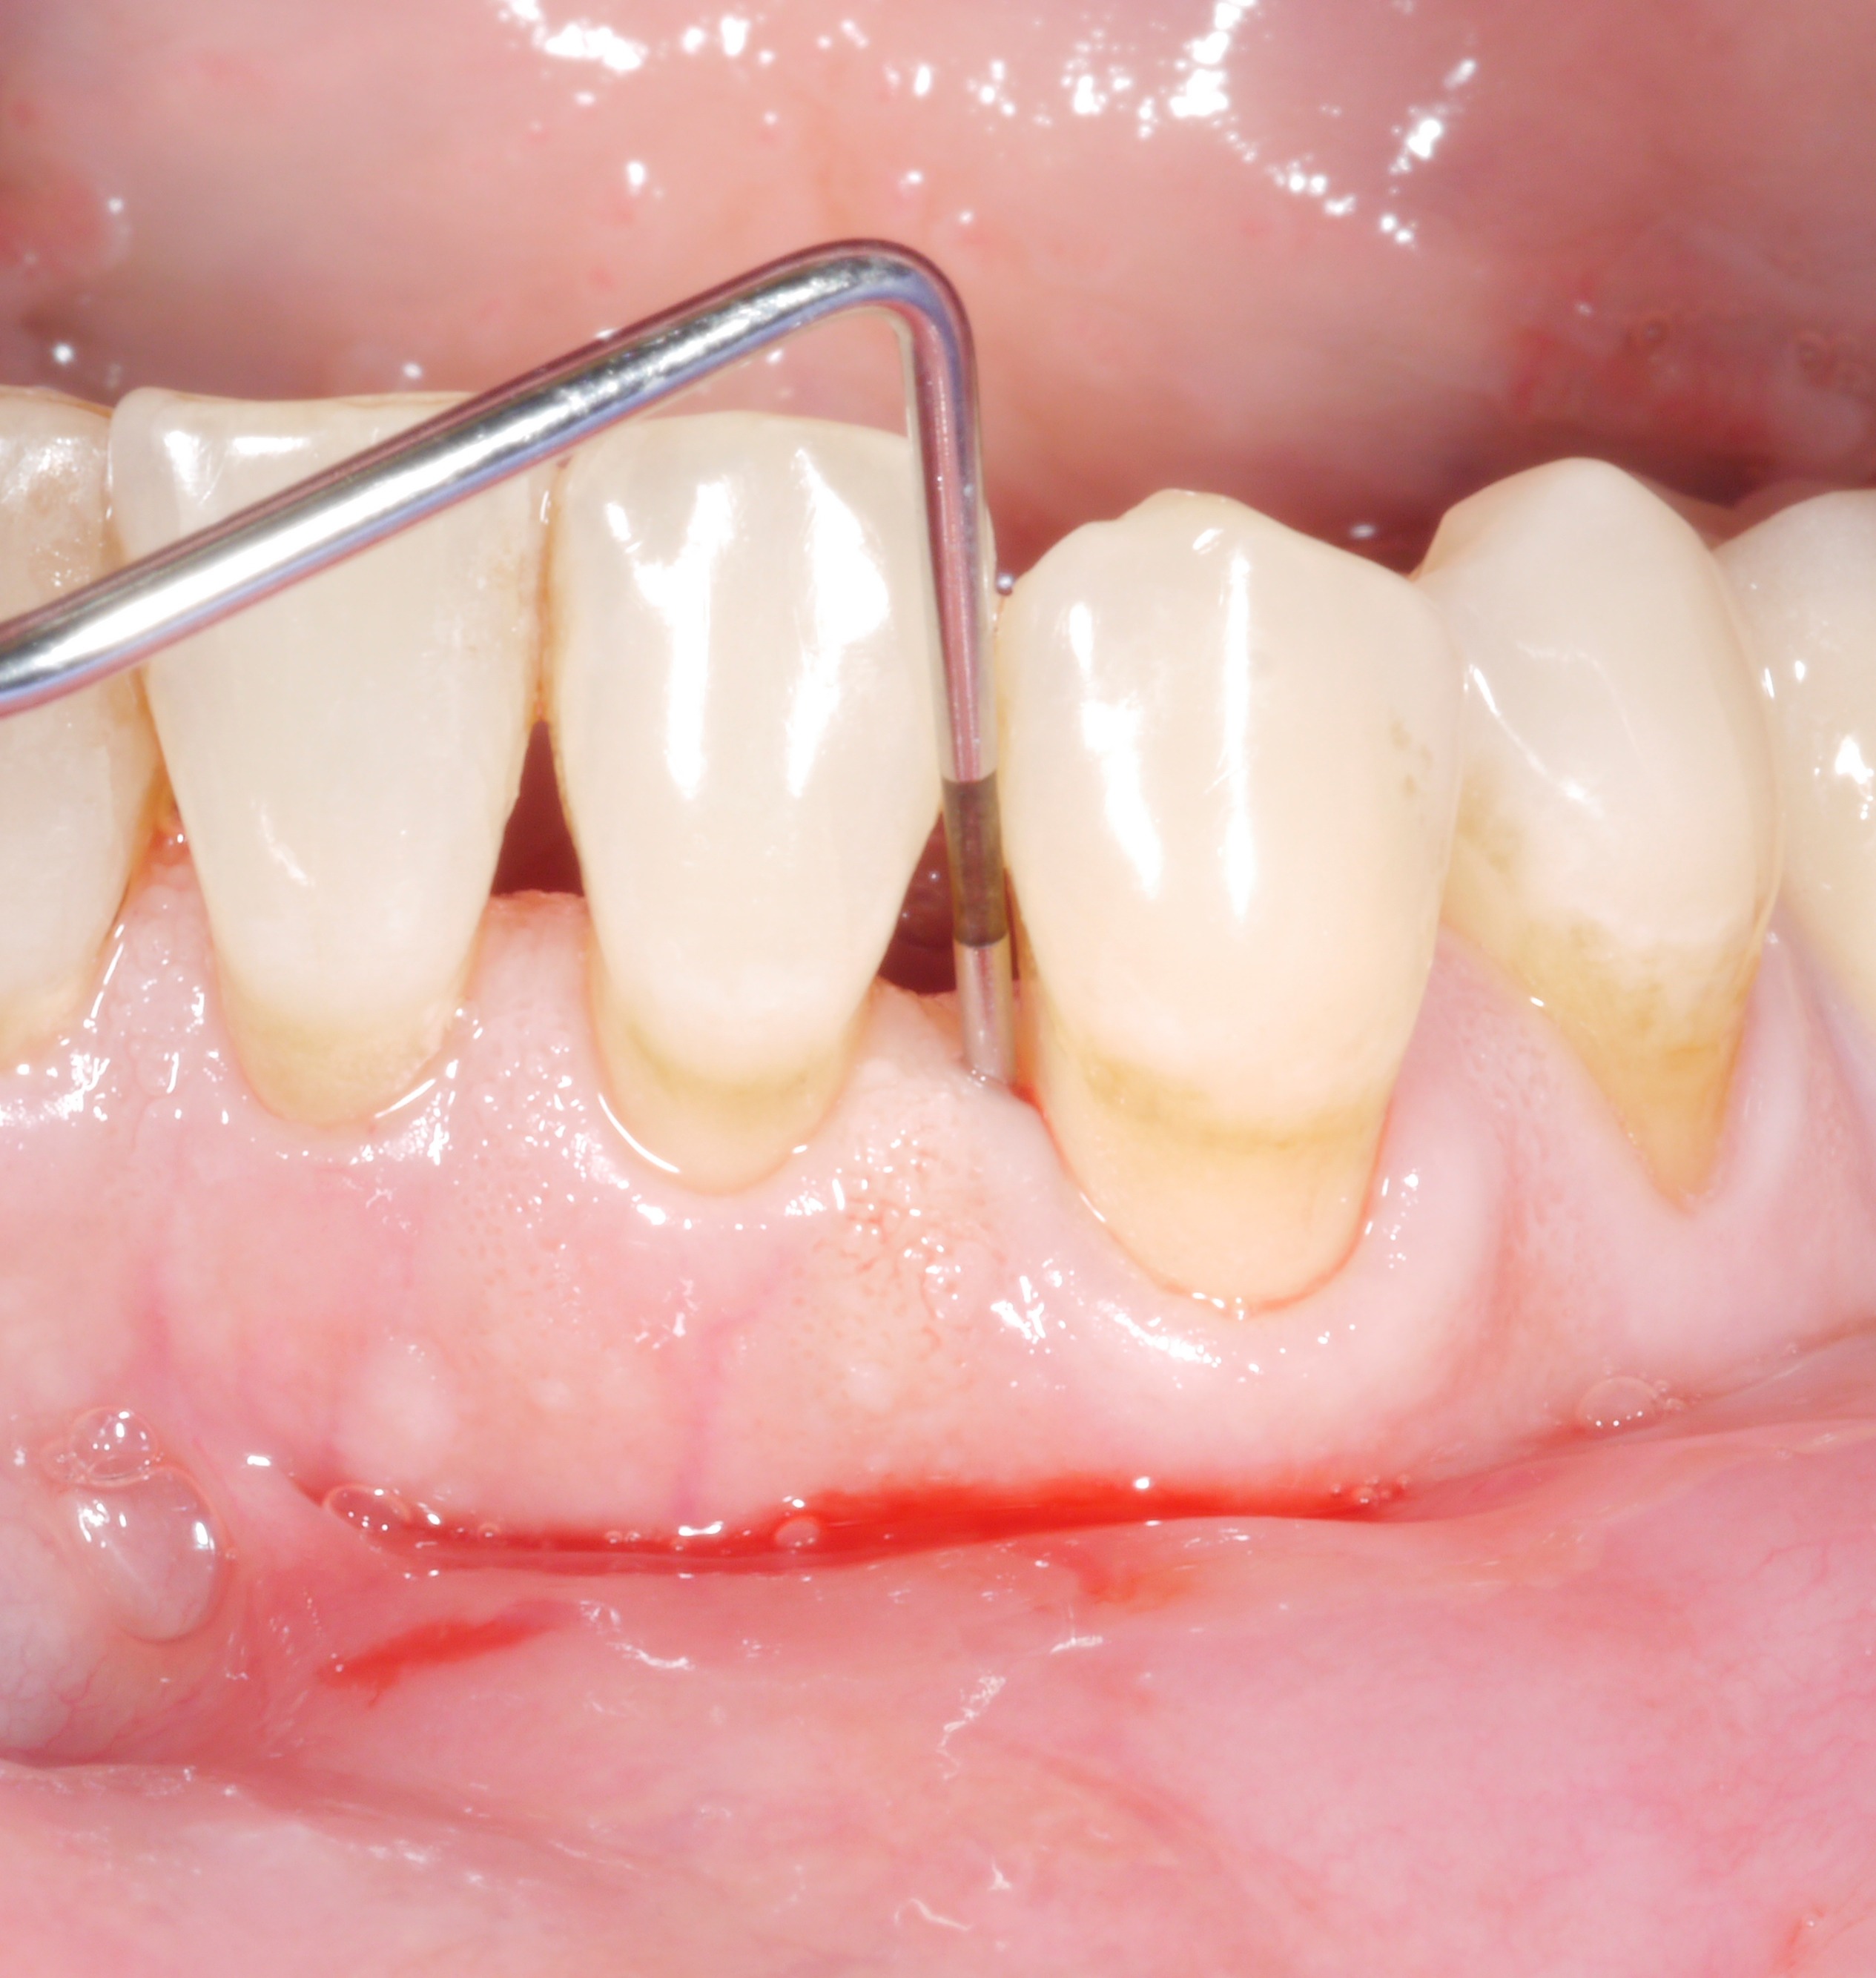

It is a situation we are all too familiar with: following the active phase of treatment, nearly all the patient’s teeth are now unaffected by increased pocket probing depths. However, there are still 1 or 2 places where the treatment goal has unfortunately not been achieved. The following thought might arise: “how bad can it be? A single pocket of 6 or 7 mm – surely that can’t make a big difference?

However, dentists should not rush to say they are content with residual pocket probing depths. This is because even individual residual pocket probing depths of more than 4 mm constitute a problem, as least in the longer term – both for the affected tooth and for the rest of the dentition.

• Bleeding on probing doubled the risk of later tooth loss.

• The risk of tooth loss was almost 8 times higher for a pocket probing depth (PPD) of 5 mm, about 10 times higher for a PPD of 6 mm, and more than 60 times higher for a PPD of 7 mm!

Conclusion: The treatment goal should be to achieve pocket probing depths of 4 mm maximum and an absence of inflammation!